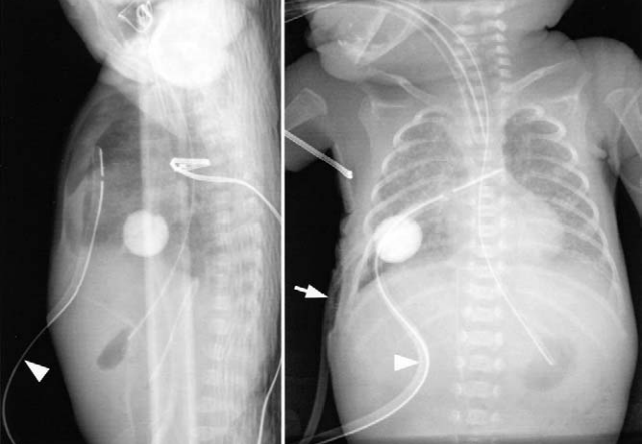

McElroy et al used a Foley catheter to control chest wall bleeding in a preterm infant that had a lacerated intercostal artery from prior chest tube insertion.

(article is open access)

jpeds.com